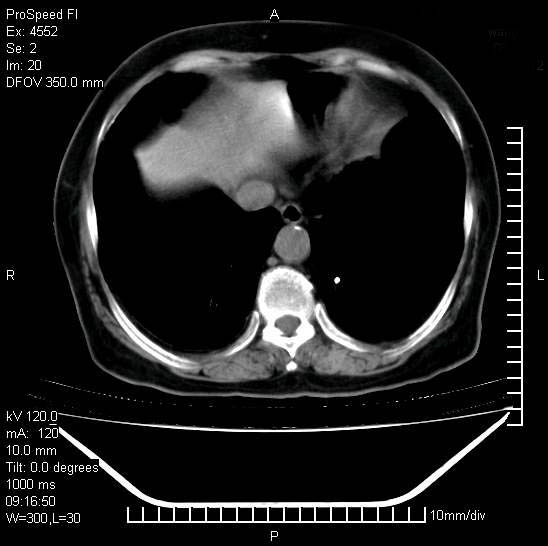

标题: CT15528:女性,79岁,近几日晚上高热,39度,仍咳少量血 [打印本页]

十几年前曾患肺结核,一周前突咳血约100ml,中性粒细胞稍高,诊断两上肺陈旧结核,下肺炎症,给予抗炎治疗,近几日晚上高热,39度,仍咳少量血,4天前ct及今天ct上传。

[face=黑体]8月30日[/face]

支持陈旧性肺结核并两下肺感染,两侧胸腔积液。

短短几天内,病变范围明显增多扩大,以左侧明显,而且双侧出现胸水,还是考虑感染.

短短几天内,病变范围明显增多扩大,以左侧明显,而且双侧出现胸水,我更多考虑左侧中心性肺癌并并阻塞性不张及肺炎,炎症变化也太快了!

1)两肺结核并感染。2)不排除左肺上叶中央型肺癌并阻塞性肺炎、肺不张可能;建议行纤支镜检查。3)右肺门及纵隔淋巴结肿大。4)双侧胸腔积液。

陈旧性肺结核及左下肺不张,咯血后肺部感染,双胸腔积液,高热可能与痰液引流不畅有关。